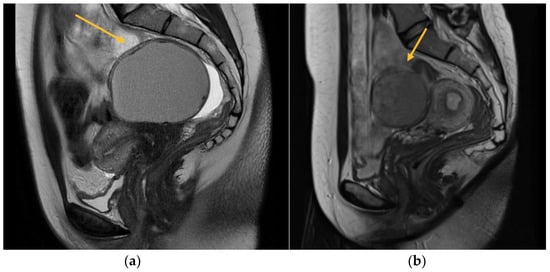

As will be elaborated upon in the forthcoming discussion section, the identification of parametrial lesions may prove more challenging in the absence of collaboration with a radiologist possessing specialized expertise in recognizing DIE lesions. The parametrial nodule manifests as a hypointense thickening or evidence of a mass with irregular contours situated in the posterior uterine region, as depicted in Figure 4 [16].

Regarding MRI diagnosis of bowel DIE nodules, Figure 7 illustrates the presence of nodular thickening, which leads to anatomical deformation of the intestinal loop. The rectal nodule is adherent to the posterior uterine wall through an adenomyosis lesion, as indicated by the yellow arrow. Rectal DIE nodules typically exhibit adherence to other DIE lesions, including uterine torus, USL, parametrial, or adenomyosis [13,14].

Figure 1. MRI aspect on T2 sagittal (a) Left endometrioma with left ovary adherent to the posterior uterine wall (b) Right endometrioma.

Figure 7. MRI aspect on T2 sagittal (A,B): recto-sigmoidian endometriosis nodule adherent to the uterine fundus via adenomyosis lesion.